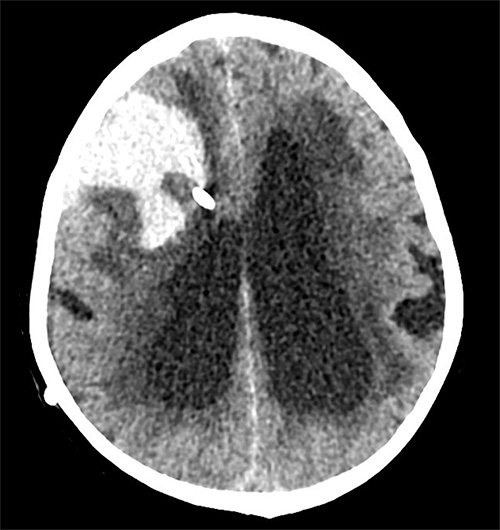

Axial DT-bild av patient som drabbades av en allvarlig blödningskomplikation frontalt höger utmed shuntslangens förlopp. Blödningen inträffade inom 48 timmar postoperativt.